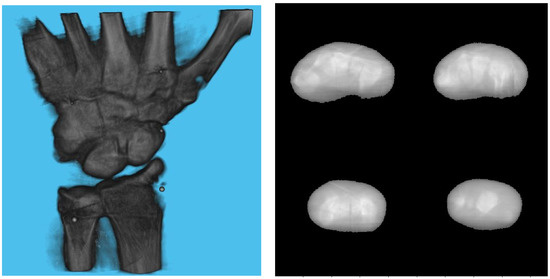

3. Experiments and Results

3.1. Simulation Setup